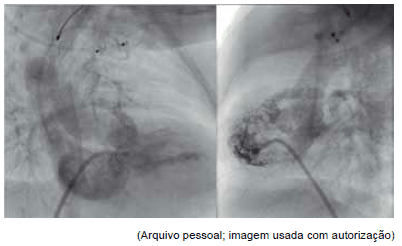

Observe as seguintes figuras de cateterismo cardíaco para responder à questão.

Com relação às figuras, o diagnóstico mais provável da cardiopatia congênita é: